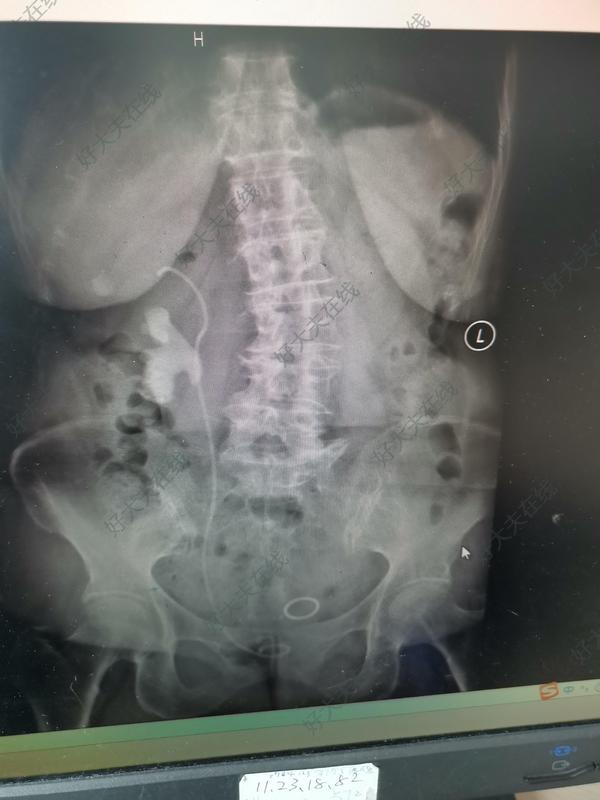

治療前 老年女性右側腰部疼痛1周入院,入院后檢查發(fā)現(xiàn)右腎鑄型結石,既往做過經皮腎鏡手術,住院檢查發(fā)現(xiàn)該患者右腎為重復腎,重復輸尿管。 治療中 碩通鏡聯(lián)合輸尿管軟鏡二期完全清石。 治療后 治療后3天 患者出院后無腰痛,無血尿,該手術方式風險小,無經皮腎鏡的穿刺出血風險。